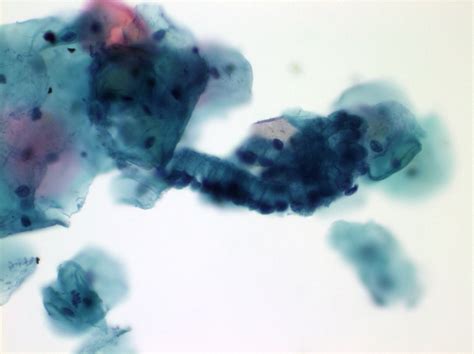

Understanding the significance of the endocervical component present in Pap smear results is crucial for both healthcare providers and patients. This component refers to the presence of cells from the endocervix, the inner lining of the cervix, in a Pap smear sample. The detection of these cells can provide valuable insights into the health of the cervix and help in the early detection of cervical cancer and other cervical abnormalities.

The endocervical component refers to the presence of cells from the endocervix in the Pap smear sample. The endocervix is the inner lining of the cervix, which is the lower part of the uterus that connects to the vagina. The presence of these cells can indicate that the sample was collected adequately and that the entire transformation zone, the area where most cervical cancers develop, was sampled.

• Endocervical Component Present: This notation in the report confirms that the sample included cells from the endocervix, ensuring a more comprehensive evaluation.